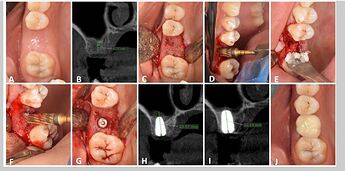

Densah Bur Group. A : Preoperative clinical view, B : preoperative CBCT, C : Full thickness mucoperiosteal flap, D : Densah sinus floor elevation, E & F : Allograft application, G : Implants after placement, H : Immediate postoperative CBCT showing vertical bone height, I : CBCT after 6 months, J : occlusal view of final zirconia crown

**a** –**c** Showing sloping sinus floor and sequence of drilling using the Densah bursShowing Densah bur design

a Measuring the amount of bone gain achieved following the Densah lift. b Graft containment around the implant apex. c Angle measurement confirming a sloping sinus floor